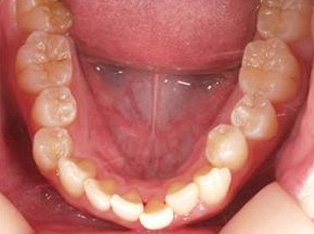

治療前

治療終了前